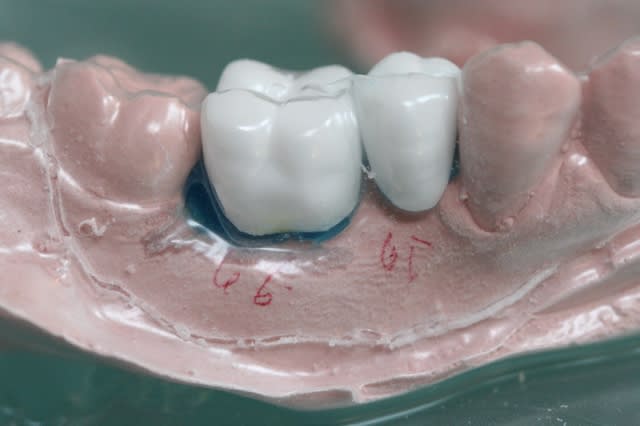

6 de la cire pour éliminer les contre dépouilles

7

8 mettre de la résine (transparente pour mieux visualiser) uniquement sur les bords occlusaux et en palatin

9

10 après polissage